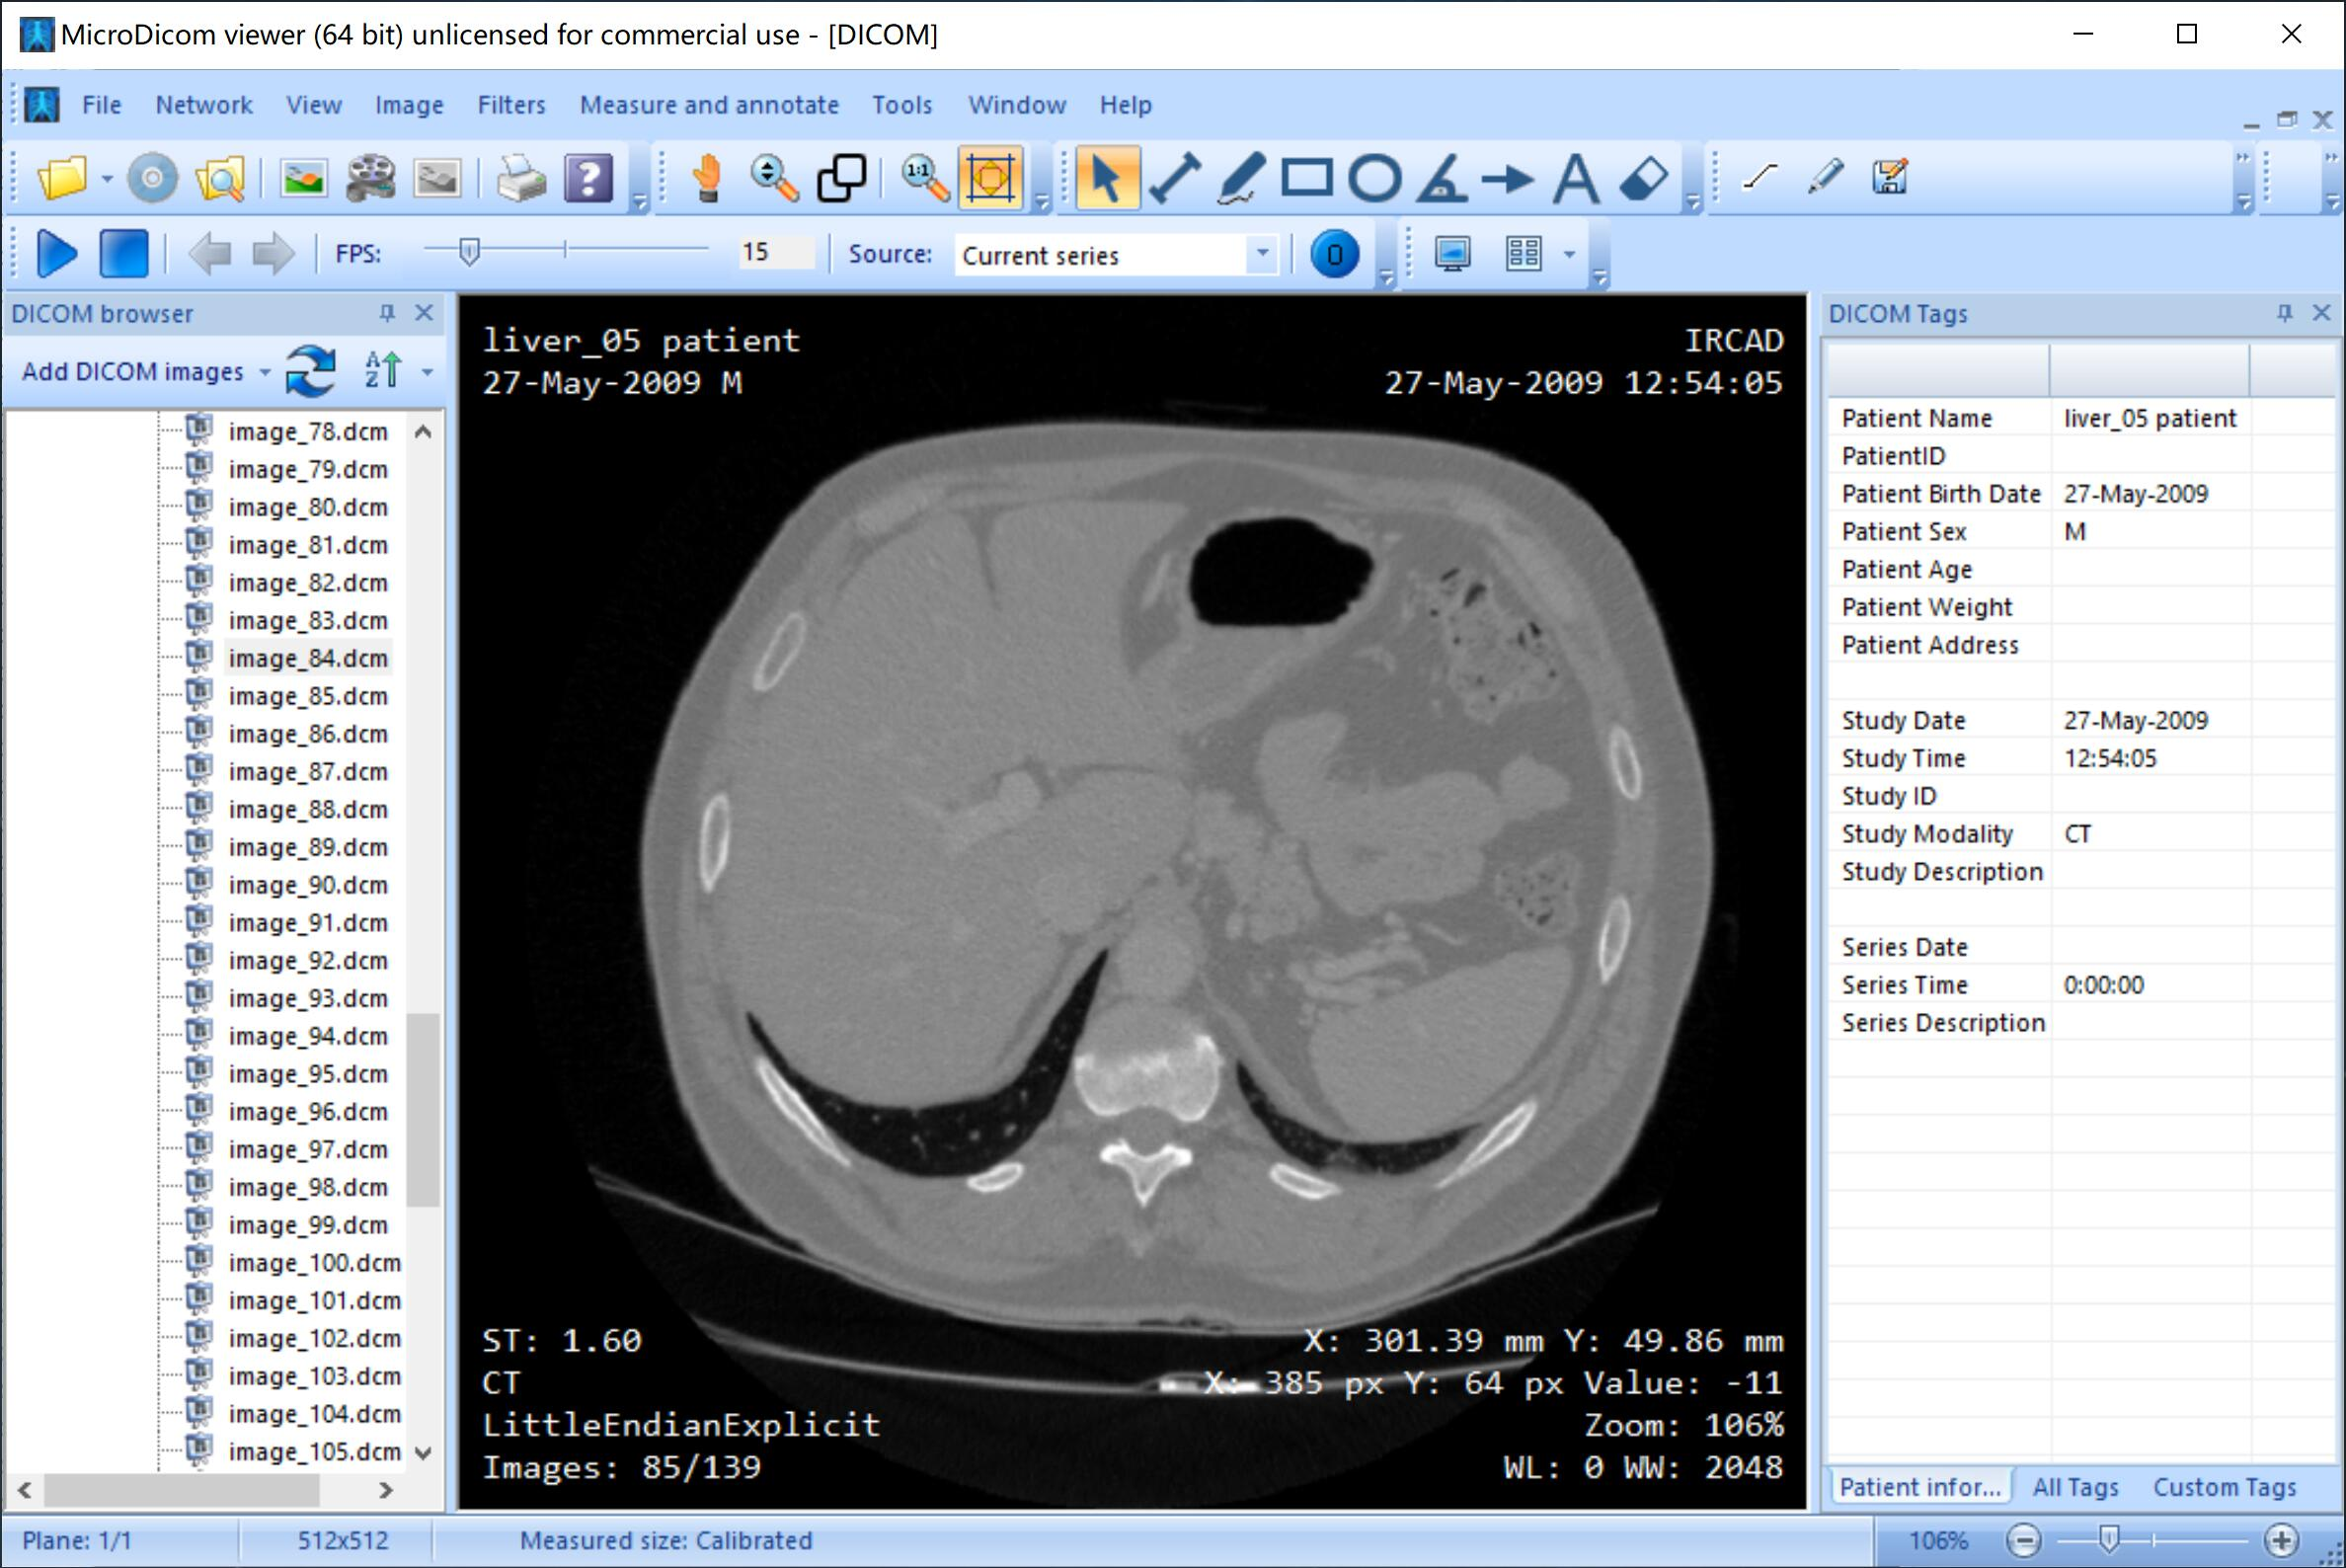

二、DICOM 文件的查看

查看 DICOM 格式图像的最简便的方式是使用软件,这里给大家推荐两个软件:MicroDicom 和 RadiAnt Viewer,前者是完全免费的,后者只能试用,后者的功能更强大,可以实现三维重建等。

1. MicroDicom 软件

MicroDicom 软件的下载地址:下载地址

一般同一个病人的一套 DICOM 图像存储在同一个文件夹中,直接在该文件夹上右键选择用 MicroDicom 打开即可,当然也可以查看某一张图像。